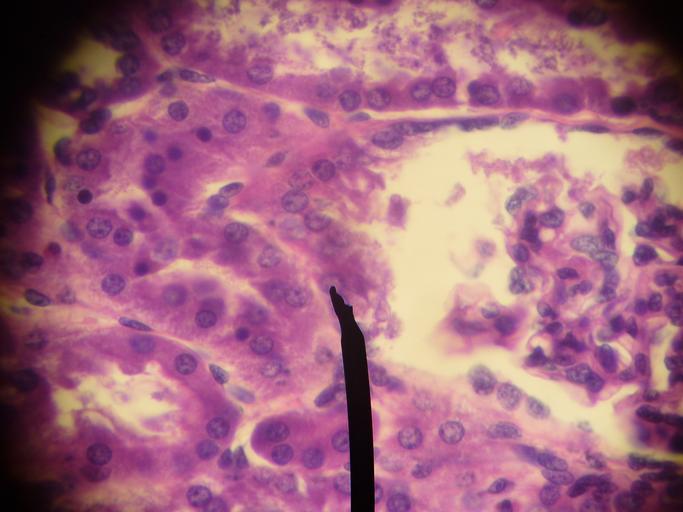

| View Original: | Juxtaglomerular cells.JPG (2816x2112) | |||

| Keywords: Juxtaglomerular cells.JPG Human JG cells Digital camera shot through a microscope own work 2007-01-20 Jpogi en wikipedia Jpogi Original upload log en wikipedia Juxtaglomerular_cells JPG 2007-01-27 10 34 Jpogi 2816×2112× 2722327 bytes <nowiki>Author' own picture Human JG cells Digital camera shot through a microscope </nowiki> Renal corpuscle | ||||